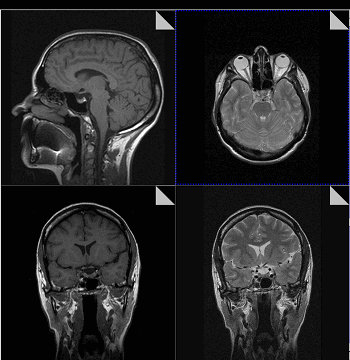

Что показывает МРТ

Магнитно-резонансная томография или МРТ - это сфокусированный метод, который проводит очень детальное обследование. Диагностическая точность МРТ превышает УЗИ и во многих случаях КТ, за исключением сканирования полых органов (легких, желудка, кишечника) и костей. МРТ является золотым стандартом диагностики:

- заболеваний головного и спинного мозга;

- патологий суставов;

- межпозвоночных дисков;

- сердца и сосудов;

- болезней гинекологического, проктологического и урологического характера.

Принцип работы МРТ основан на эффекте ядерного магнитного резонанса. МР томограф в своей конструкции имеет мощный магнит, который создает магнитное поле, и датчик, который подает радиочастотные сигналы. В такой ситуации протоны атомов водорода начинают колебательные движения, выделяя при этом импульсы. Их улавливает компьютер томографа и преобразовывает в трехмерные изображения. Чем больше воды содержится в клетках ткани, тем детальней получается ее изображение. Поэтому на МРТ хорошо отображаются органы с большим содержанием воды: МРТ головного мозга, МРТ спинного мозга, МРТ глазных орбит, МРТ органов малого таза, МРТ позвоночника, МРТ суставов, и плохо визуализируются органы с большим содержанием воздуха МРТ органов грудной клетки или кости.

Магнитно-резонансная томография

В основе МРТ лежит явление магнитного резонанса, основанного на переизлучении радиоволн, взаимодействующих с атомами водорода, в избытке содержащимися в организме человека. Эти переизлученные электромагнитные волны улавливаются датчиком МР-томографа, усиливаются и в виде цифровых изображений появляются на экране монитора. Это безвредный и абсолютно безопасный для здоровья человека метод лучевой диагностики, так как в основе получения изображения отсутствует рентгеновское излучение, поэтому МРТ можно проходить неограниченное количество раз, с любым интервалом.

Существенное преимущество МР-томографии перед КТ заключается в том, что она не противопоказана беременным во II и III триместре и совершенно безопасна для детей. В МРТ исследуемая область сканируется в трех проекциях, что позволяет врачу-рентгенологу в полной мере оценить состояние тканей и органов исследуемой области, а высокая контрастность изображения и пространственное разрешение позволяют визуализировать серое и белое вещество головного мозга, оценивать состояние костного мозга и мягких тканей различной локализации. Кроме того, метод МРТ позволяет получать изображения сосудов головного мозга и сосудов шеи без введения контрастного препарата.